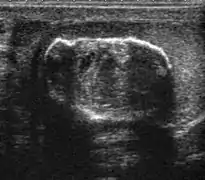

Undescended testis is found in 4% of full-term infants but only 0.8% of males at the age of 1 year have true cryptorchidism. Although an undescended testis can be found anywhere along the pathway of descent from the retroperitoneum to the scrotum, the inguinal canal is the most common site for an undescended testis. Deviation of testis from the normal pathway of descent will result in ectopic testis that is commonly seen in pubopenile, femoral triangle and perineal regions.

The incidence of infertility is decreased if surgical orchiopexy is carried out before the 1–3 years but the risk of malignancy does not change. Because of the superficial location of the inguinal canal in children, sonography of undescended testes should be performed with a high frequency transducer. At ultrasound, the undescended testis usually appears small, less echogenic than the contralateral normal testis and usually located in the inguinal region [Fig. 29]. With color Doppler, the vascularity of the undescended testis is poor.

Fig. 29. Undescended testis. (a) Normal testis in the scrotum. (b) Atrophic and decreased echogenicity of the contralateral testis of the same patient seen in the inguinal region.